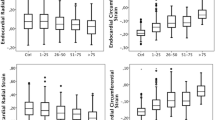

Comparison of myocardial strain with the presence and transmural extent of LGE

Differences were observed for peak Ecc measured in infarcted segments versus peak Ecc in both remote and adjacent segments, and between peak Ecc in remote and adjacent segments, at both baseline and follow-up. The results are illustrated in Fig. 3.

The results of the Kruskal–Wallis test with individual Mann–Whitney tests comparing the three categories of tissue pathology (remote, adjacent, infarcted) are illustrated in Fig. 4a. Differences were observed between the change in strain in remote and infarcted segments, and between adjacent and infarcted segments.

Within each designated pathological tissue category (remote, adjacent, infarcted), comparison of tissue categories showed no statistically significant differences when considering the change in strain between baseline and follow-up. However, differences were observed when comparing baseline strain between sub-categories, as illustrated in Fig. 4b.